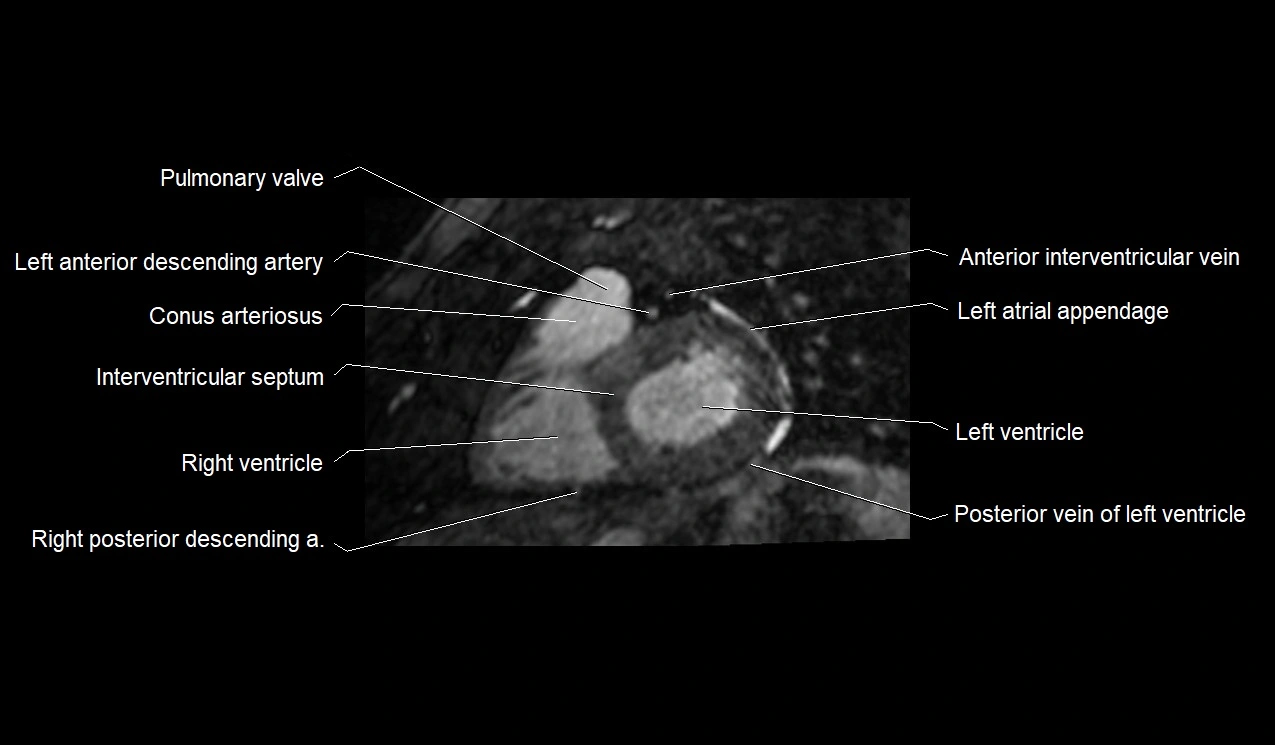

MRI image